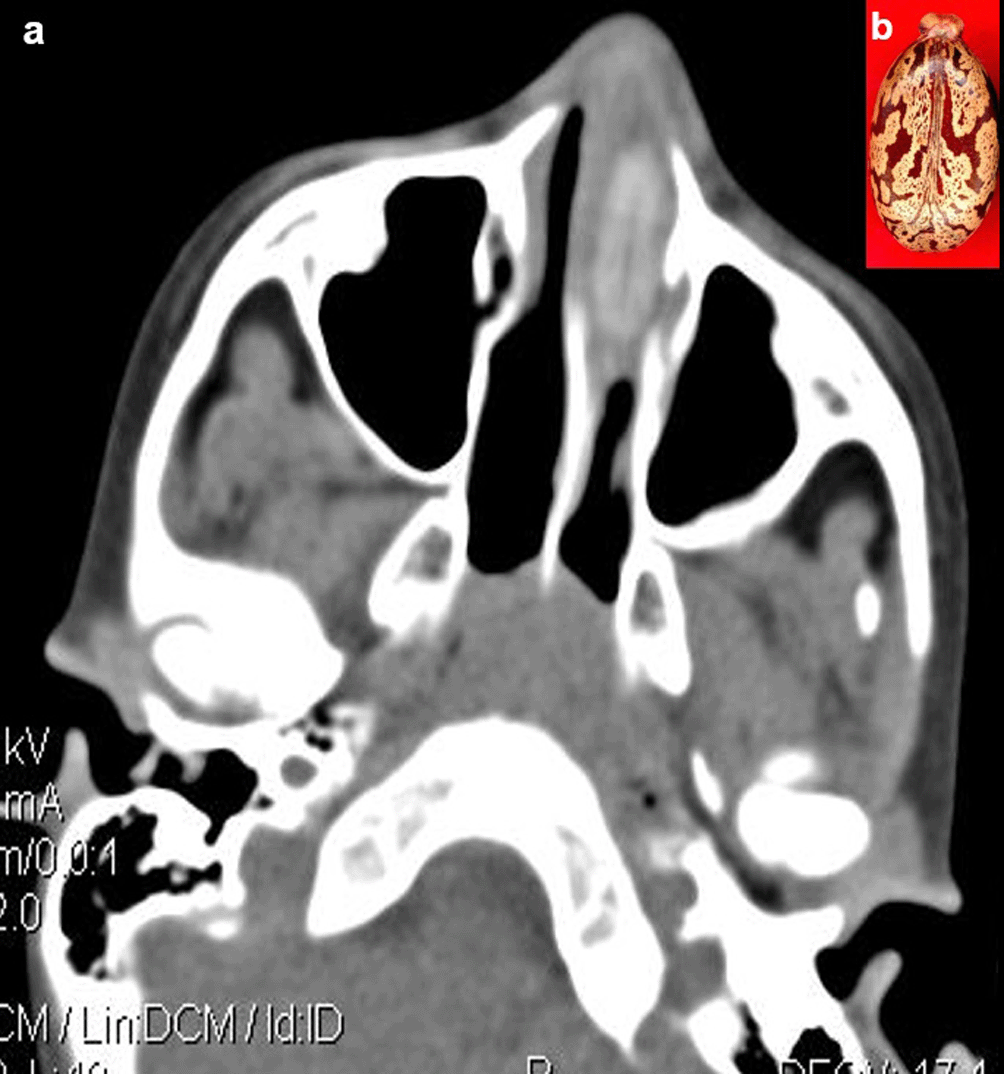

Case 5: A seven-year-old boy came with a history of epistaxis. CT paranasal sinuses (PNS) revealed a non-enhancing hyperdense lesion in the left nasal cavity, possibly a foreign body. It was removed under anaesthesia and found to be a castor seed.

When a patient cannot provide a sufficient history or has swallowed things that are not naturally radio-opaque, the diagnosis of an ingested foreign body is frequently missed. If a foreign body is suspected and is not visible on a Radiograph because of its radiolucent nature, a CT scan of the abdomen or chest may be beneficial8 (Figure 4a,b).